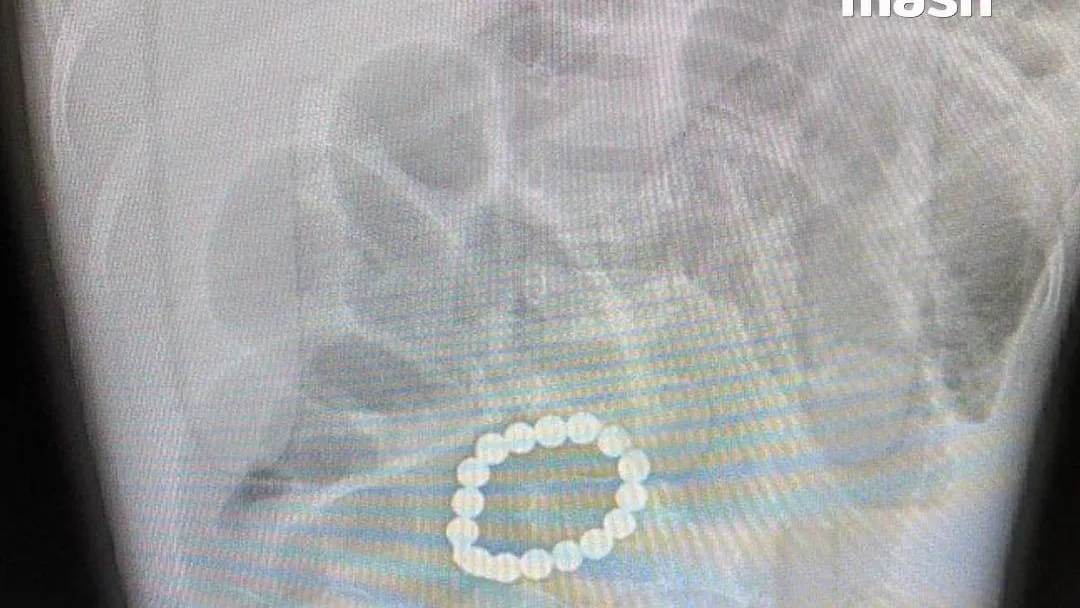

Тромб — это некое формирование из плотных масс крови, которое, путешествуя по сосудам человека вместе с кровью, может перекрыть их, что приведет к непредсказуемым последствиям и даже летальному исходу.

Оторвавшись от места прикрепления, тромб «гуляет» по организму как мина замедленного действия и в любой момент он может преподнести страшный сюрприз, спровоцировав инфаркт, инсульт или мгновенную смерть.